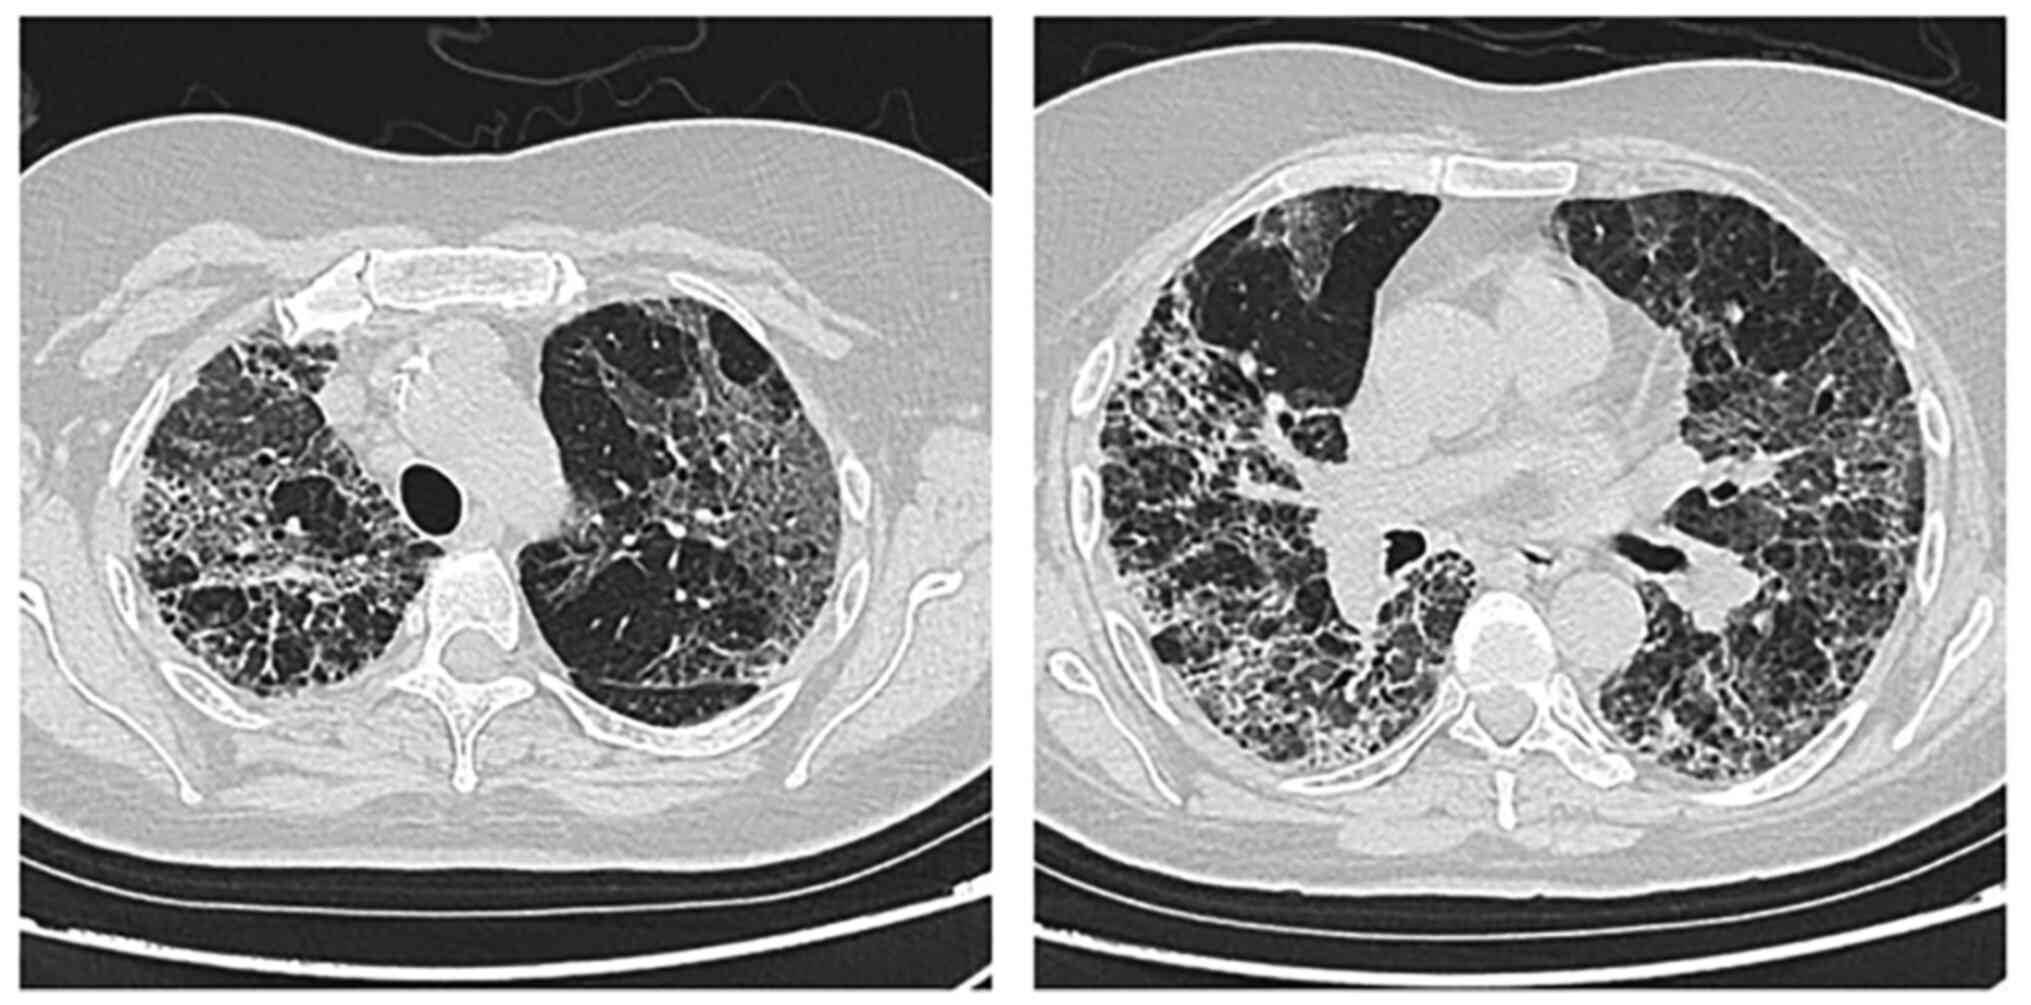

A 73-year-old woman was admitted in May 2021 to the Department of Infectious Disease in the Clinical Infectious Diseases Hospital with a cough, shortness of breath and fatigue that was found to be due to severe SARS-CoV-2 pneumonia by nasopharyngeal swab. The patient had multiple cardiovascular risk factors, including arterial hypertension, type 2 diabetes mellitus, obesity (36.7 BMI) and a history of coronary heart disease for a number of years. Chest X-rays showed bilateral pneumonia with peripheral consolidations and a reticular pattern due to septal thickening with ground-glass opacities (Fig. 1). From admission, the patient exhibited dyspnea, with acute respiratory failure (mixed venous oxygen saturation, 78%), and blood tests showed inflammatory syndrome [elevated erythrocyte sedimentation rate (80 mm/h; cut-off, 3-9 mm/h), and fibrinogen (820 mg/dl; cut-off, 196-372 mg/dl), C reactive protein (120 mg/l; cut-off, 0-5 mg/dl), ferritin (1,206 ng/ml; cut-off, 70-435 ng/ml) and IL-6 (276 pg/ml; cut-off, 0-7 pg/ml) levels]. The serum level of procalcitonin was normal. The patient received corticosteroid therapy (8 mg dexamethasone twice daily) from admission, as well as tocilizumab (2x800 mg twice daily), remdesivir (200 mg on day 1, then 100 mg daily for 5 days) and prophylactic low molecular weight heparin (4,000 IU enoxaparin daily). The clinical and biological evolution was favorable during the first hospitalization period, but on the 14th day, the patient developed a fever (38.5˚C temperature) and their general condition worsened. Laboratory tests revealed a high procalcitonin level of 4.1 ng/ml (cut-off <0.5 ng/ml), mildly elevated liver transaminase levels (ALT, 120 u/l; cut-off, 4-36 U/l; AST, 163 U/l; cut-off, 5-40 U/l) and a decreased estimated glomerular filtration rate (41 ml/min/1.73 m2). The hs-troponin (152 ng/l; cut-off, 4.9-50 ng/l) and D-Dimer (1.78 µg FEU/ml; cut-off, 0-0.5 µg FEU/ml) levels were also elevated. The patient developed respiratory distress (arterial oxygen partial pressure/fractional inspired oxygen ratio <100) that required non-invasive continuous positive airway pressure ventilation. A pulmonary computed tomography scan was therefore performed, which ruled out a pulmonary embolism and showed diffuse ground-glass opacities, peripheral consolidation and bronchiectasis (Fig. 2). Blood cultures were positive for Enterococcus faecium sensible to vancomycin, linezolid, teicoplanin and tigecycline.

Figure 2

Computed tomography images showing diffuse ground-glass opacities, peripheral consolidation and bronchiectasis.